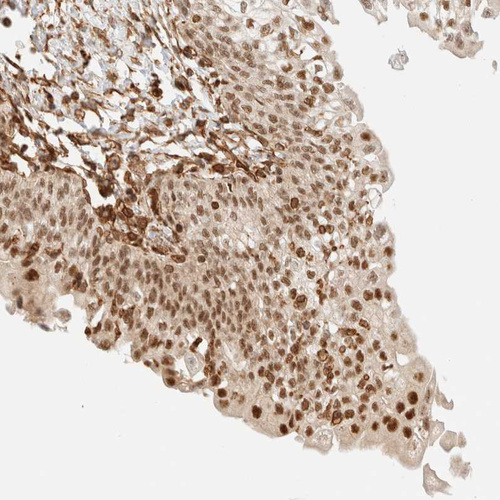

Immunohistochemical staining of human urinary bladder shows strong nuclear positivity in urothelial cells.